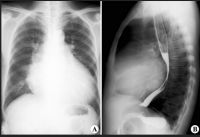

1.X线检查:心影扩大,晚期外观如球形,说明各心腔均增大,外形颇似心包积液。少数患者以左心室、左心房或右心室增大为主,外观类似二尖瓣病变。透视下见心脏搏动较正常为弱。主动脉一般不扩大。病程较大的患者常有肺瘀血和肺间质水肿,两肺肋膈角处可有间隔线,肺静脉肺动脉影可扩大;胸腔积液不少见。

扩张型心肌病X线改变